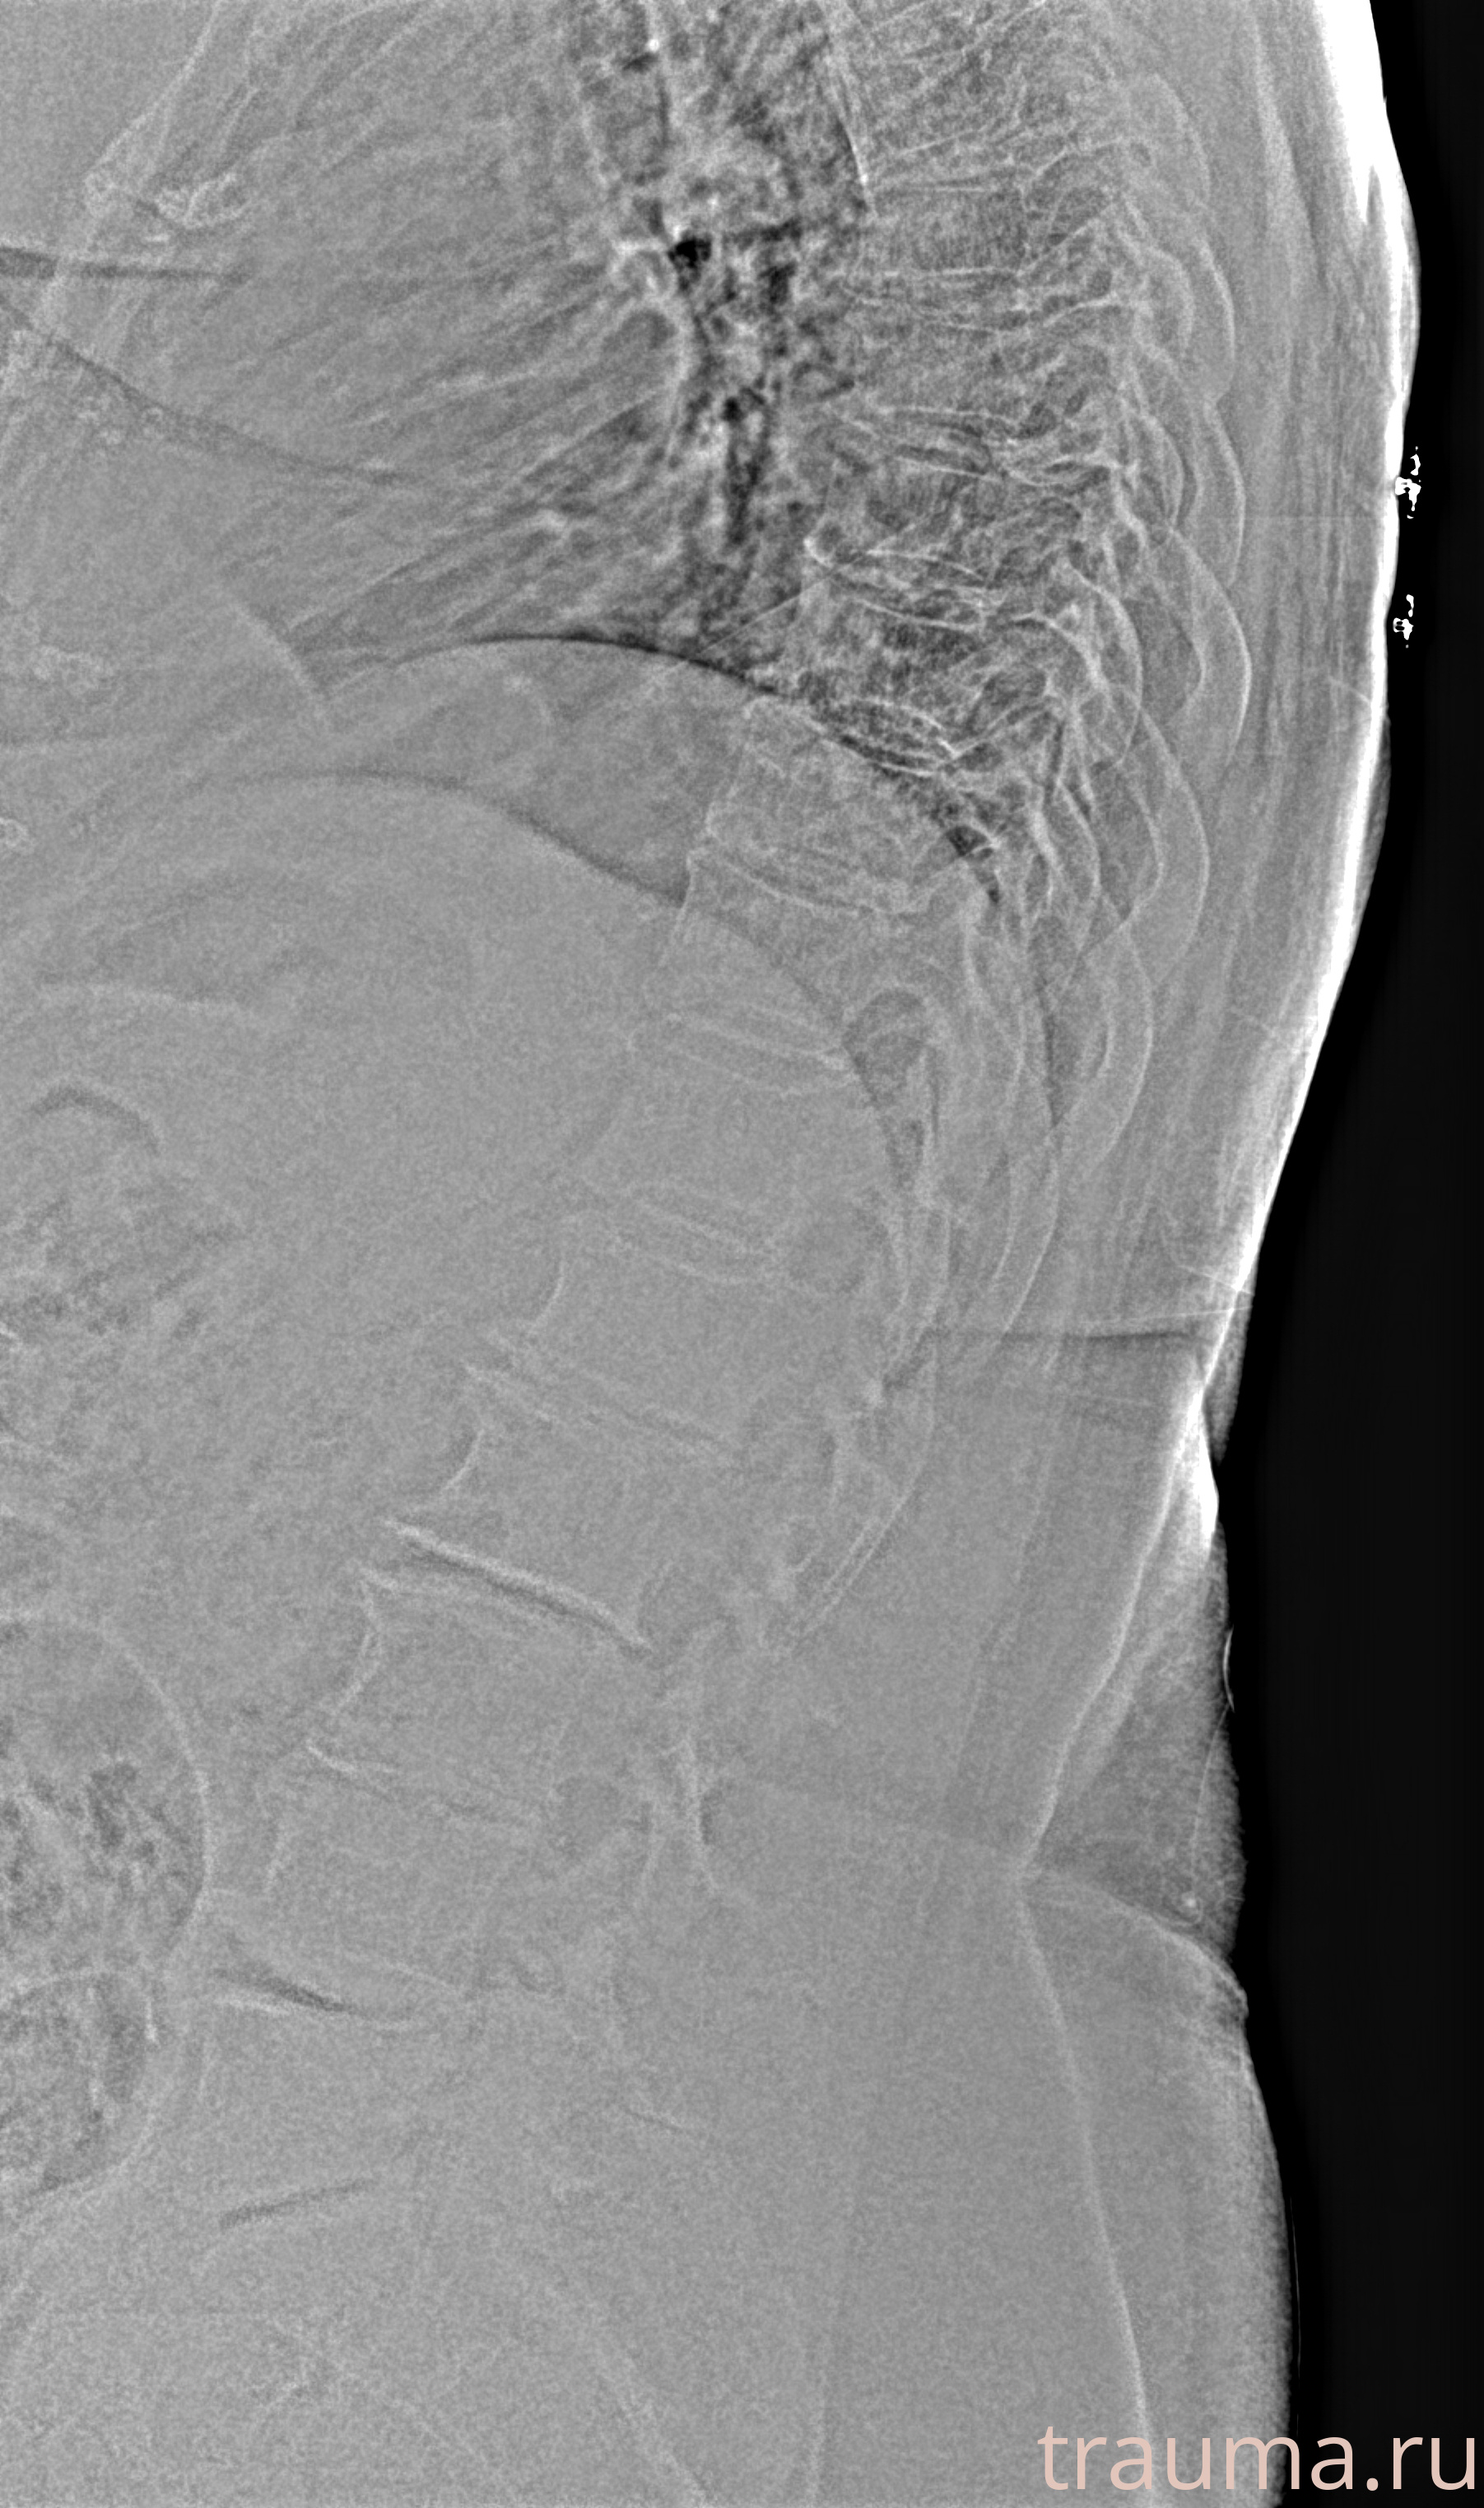

Рентгенограммы

Рентген на дому: по вашему адресу приезжает врач-рентгенолог, травматолог-ортопед с мобильным рентгеновским аппаратом, проводит диагностику травмы или заболевания, делает необходимые рентгенограммы, дает рекомендации по дальнейшему лечению. Получить качественные снимки в домашних условиях возможно благодаря уникальной методике, разработанной МосРентген Центром для института  Склифосовского